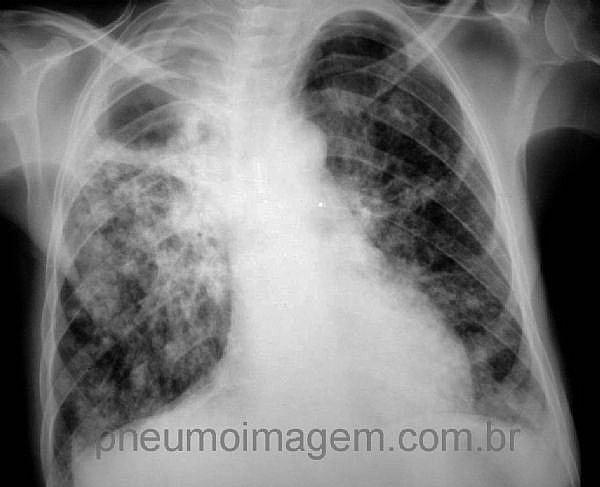

NOVAS DIRETRIZES PARA TUBERCULOSE DO NICE (2016): CLIQUE AQUI.As Diretrizes/Guidelines de prática clínica de 2016 do National Institute for Health and Care Excellence (NICE) a respeito da tuberculose foram lançadas em janeiro e atualizadas em maio de 2016. As novas diretrizes trazem recomendações para a sua prevenção; tratamento da tuberculose latente, ativa e resistente a drogas; o controle de infecção; o rastreamento ativo; aderência, finalização de tratamento e seguimento e da organização dos serviços especializados.